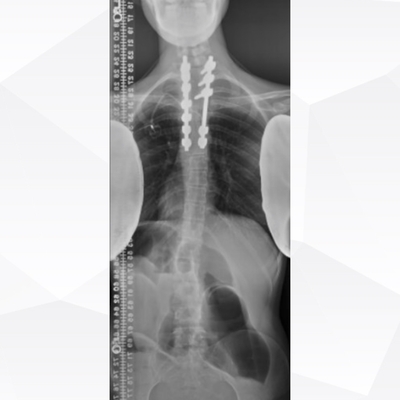

Click on an image below to view more info.